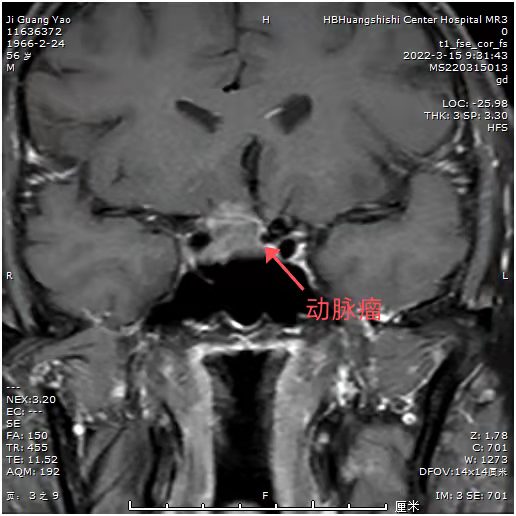

患者近期视力明显下降,一侧视力只有0.1,而且感觉眼部肿胀不适。MRI:发现鞍区占位。常规CTA,发现鞍区小动脉瘤!如果先处理动脉瘤,介入需支架辅助,术后需口服抗凝药物,近期3个月内,不能手术。患者必将失明!怎么办?和患者及科室血管介入组沟通后,患者意愿强烈,先行垂体瘤手术,做好术中动脉瘤破裂可能,带上动脉瘤夹,备用。

可见动脉瘤和垂体瘤很近